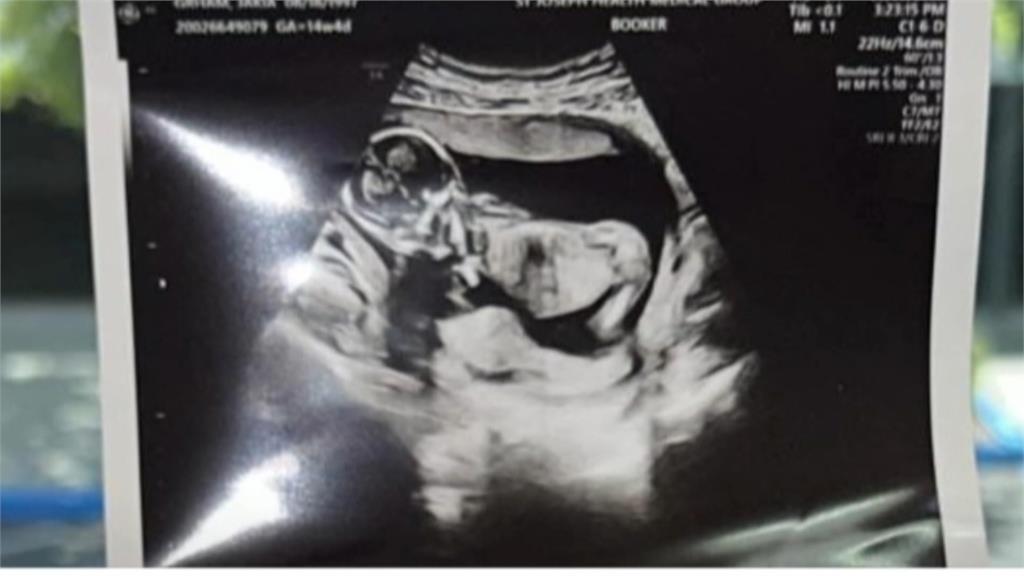

目前在台躥禁止代理孕母,但日前有對同志情侶,在社群分享,自己在墨西哥,找了兩個代理孕母,生下四胞胎的故事,引發網友炸鍋!波還沒平息,又有名慈濟醫院的吳姓骨科醫師,po出代理孕母完整生產影片,被砲轟跟拍動物生產畫面一樣!代理孕母議題,再度浮上檯面,衛福部表示,持保留態度。

一對完全沒有生育經驗的同志網紅,高調分享在墨西哥找了兩個代理孕母,各生下一對雙胞胎。本來當作一段溫馨故事,卻在網路引起論戰!網友批評忽視代理孕母付出,質疑買小孩賺流量。

在國內代理孕母至今仍不合法,話題還在燒,沒想到又有人上傳代理孕母無碼分娩影片被炎上!

Po影片的男子被起底,還是骨科醫師。他聲稱影片都有經過孕母同意,說自己基因不是特別好,只是個愛孩子的普通人。卻自曝醫生曾建議幫寶寶檢查,被他回絕,認為產檢都正常,有什麼好做的?網友開轟,無法想像是何等的自大與高傲,才會找代孕還把孕母分娩的影片發出來、跟拍動物生產畫面一樣。院方則說,這是醫師私領域個人行為,要他妥善面對與處理。